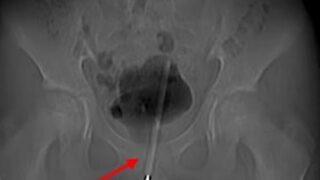

12 yaşındaki çocuğun penisinden termometre çıkması herkesi şaşkına çevirdi! Anne korkuyla hastaneye koştu

Çin’in Chengdu şehrinde yaşayan ismi açıklanmayan 12 yaşındaki bir erkek çocuğu cinsel organına bir termometreninin tamamını soktu. Cinsel deney yapmak istediğini dile getiren çocuk şiddetli ağrı ve idrar problemi yaşayınca annesine durumu itiraf etti. Anne korkuyla oğlunu hastaneye götürdü.